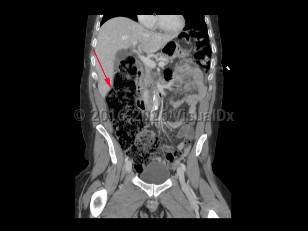

Imaging Studies image of Large bowel obstruction - imageId=8359789. Click to open in gallery.  caption: '<span>Coronal image from a CT scan demonstrating dilated ascending colon with large amount of stool. The remainder of the large bowel loops were also dilated, consistent with a large bowel obstruction.</span>'

Coronal image from a CT scan demonstrating dilated ascending colon with large amount of stool. The remainder of the large bowel loops were also dilated, consistent with a large bowel obstruction.